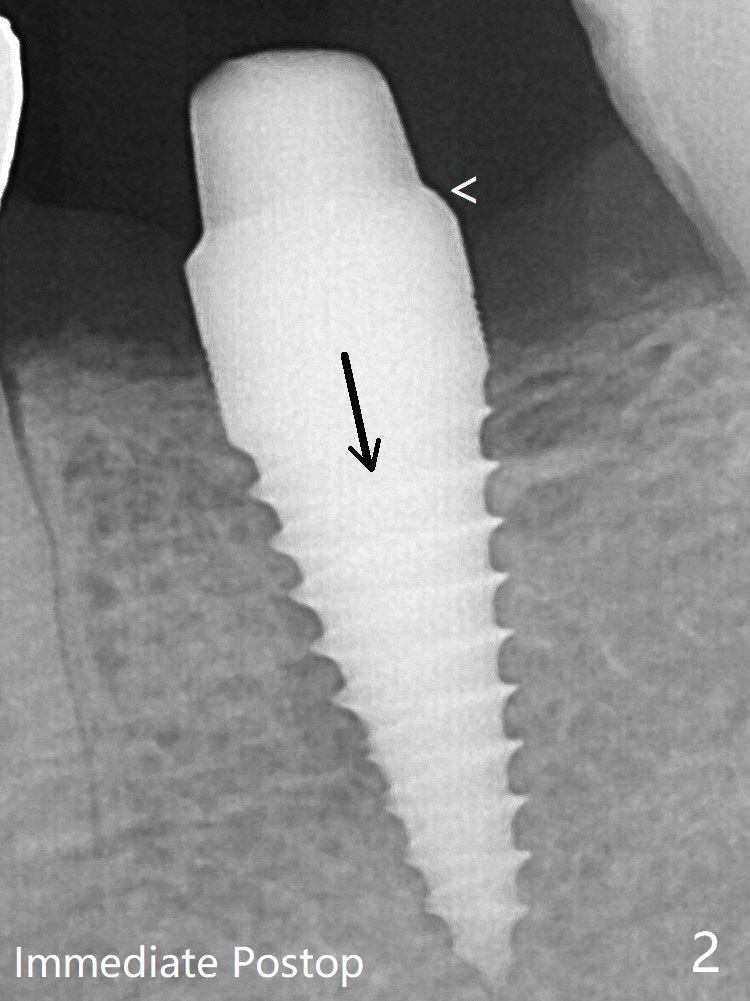

病人抱怨用临时牙冠咀嚼疼痛,不咬后没有不舒服,其实临时牙冠咬合面穿孔,牙龈正常,永久粘固剂没有外溢(图七)。术后4.5-6个月植体周围骨质吸收(图六,七:箭头)。牙槽嵴处钻洞应与植体直径一样才能减少骨质吸收。